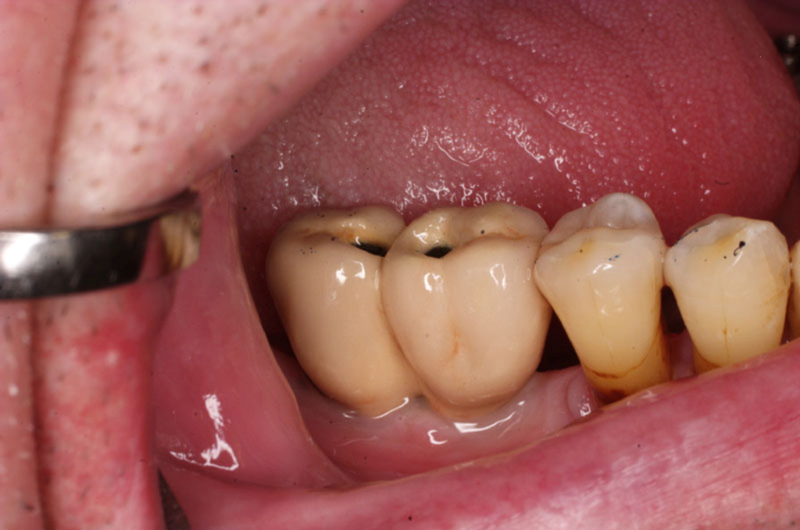

Náhrada jednoho zubu pomocí implantátu je možná také v postranním úseku chrupu. Při ztrátě většího počtu zubů ve frontálním nebo postranním úseku může být mezer uzavřena větším počtem jednotlivých implantátů.

Při ošetření pomocí jednotlivých implantátů zůstávají sousední zuby neporušené – intaktní. Při klasickém ošetření pomocí můstků musejí být tyto zuby obroušeny!

V případě chybění většího počtu zubů v postranních úsecích čelistí je možné ošetření pomocí implantátů, které nahradí ošetření pomocí snímacích náhrad kotvených na zbývajících zubech nebo patře.

Protetické řešení může být pomocí můstku, který je kotvený na implantátech nebo pomocí jednotlivých korunek na implantátech.

V zásadě je možné do těchto můstků zařadit i přirozené zuby, zejména pokud je potřeba tyto zuby ošetřit proteticky

- korunkami. Korunky nebo můstky mohou být na implantáty nacementovány nebo přišroubovány.

Zdravé zuby zůstanou zachovány a přitom náhrady jsou pevné, jako na vlastních zubech